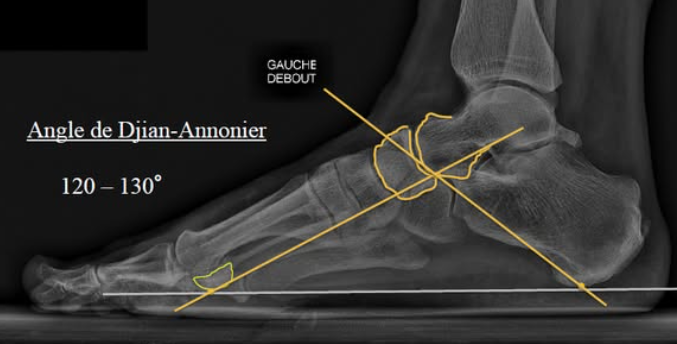

L'angle de l'arche interne du pied, mesuré sur une radio de profil en charge (Angle de Djian-Annonier), indique la cambrure :

- normal: 120° - 130°

- pied creux < 120°

- pied plat > 130° (ou 135°)